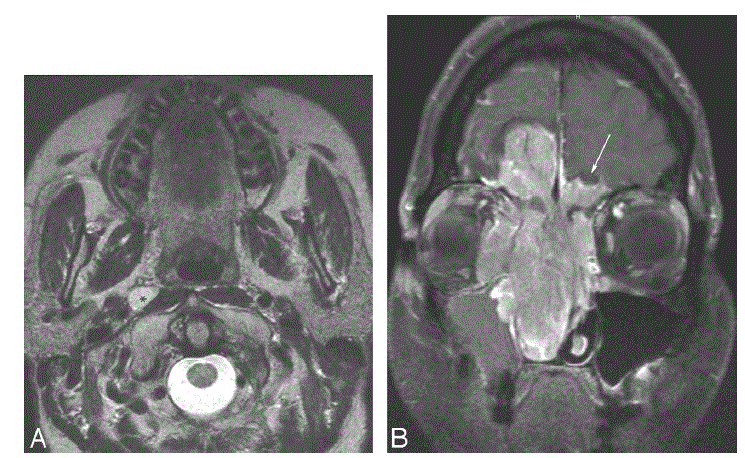

CASO 2. Homem com história de congestão nasal se apresentou em urgência hospitalar com epistaxe. Exames de imagem foram realizados:

Foi identificada uma lesão expansiva que se estendia por cavidade nasal, seios paranasais, base de crânio e apresentava metástase linfonodal.

Qual seria a classificação de Kadish modificada para o caso 2?